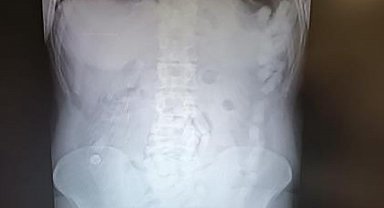

Midesinde uyuşturucu maddeyle yakalanan şahsa 12 yıl hapis cezası

03 Haziran 2025 - 14:16